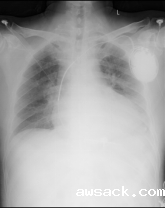

心衰超滤脱水装置: 针对充血性心力衰竭患者,实现机械性利水利钠,从而达到治疗心衰的目的。